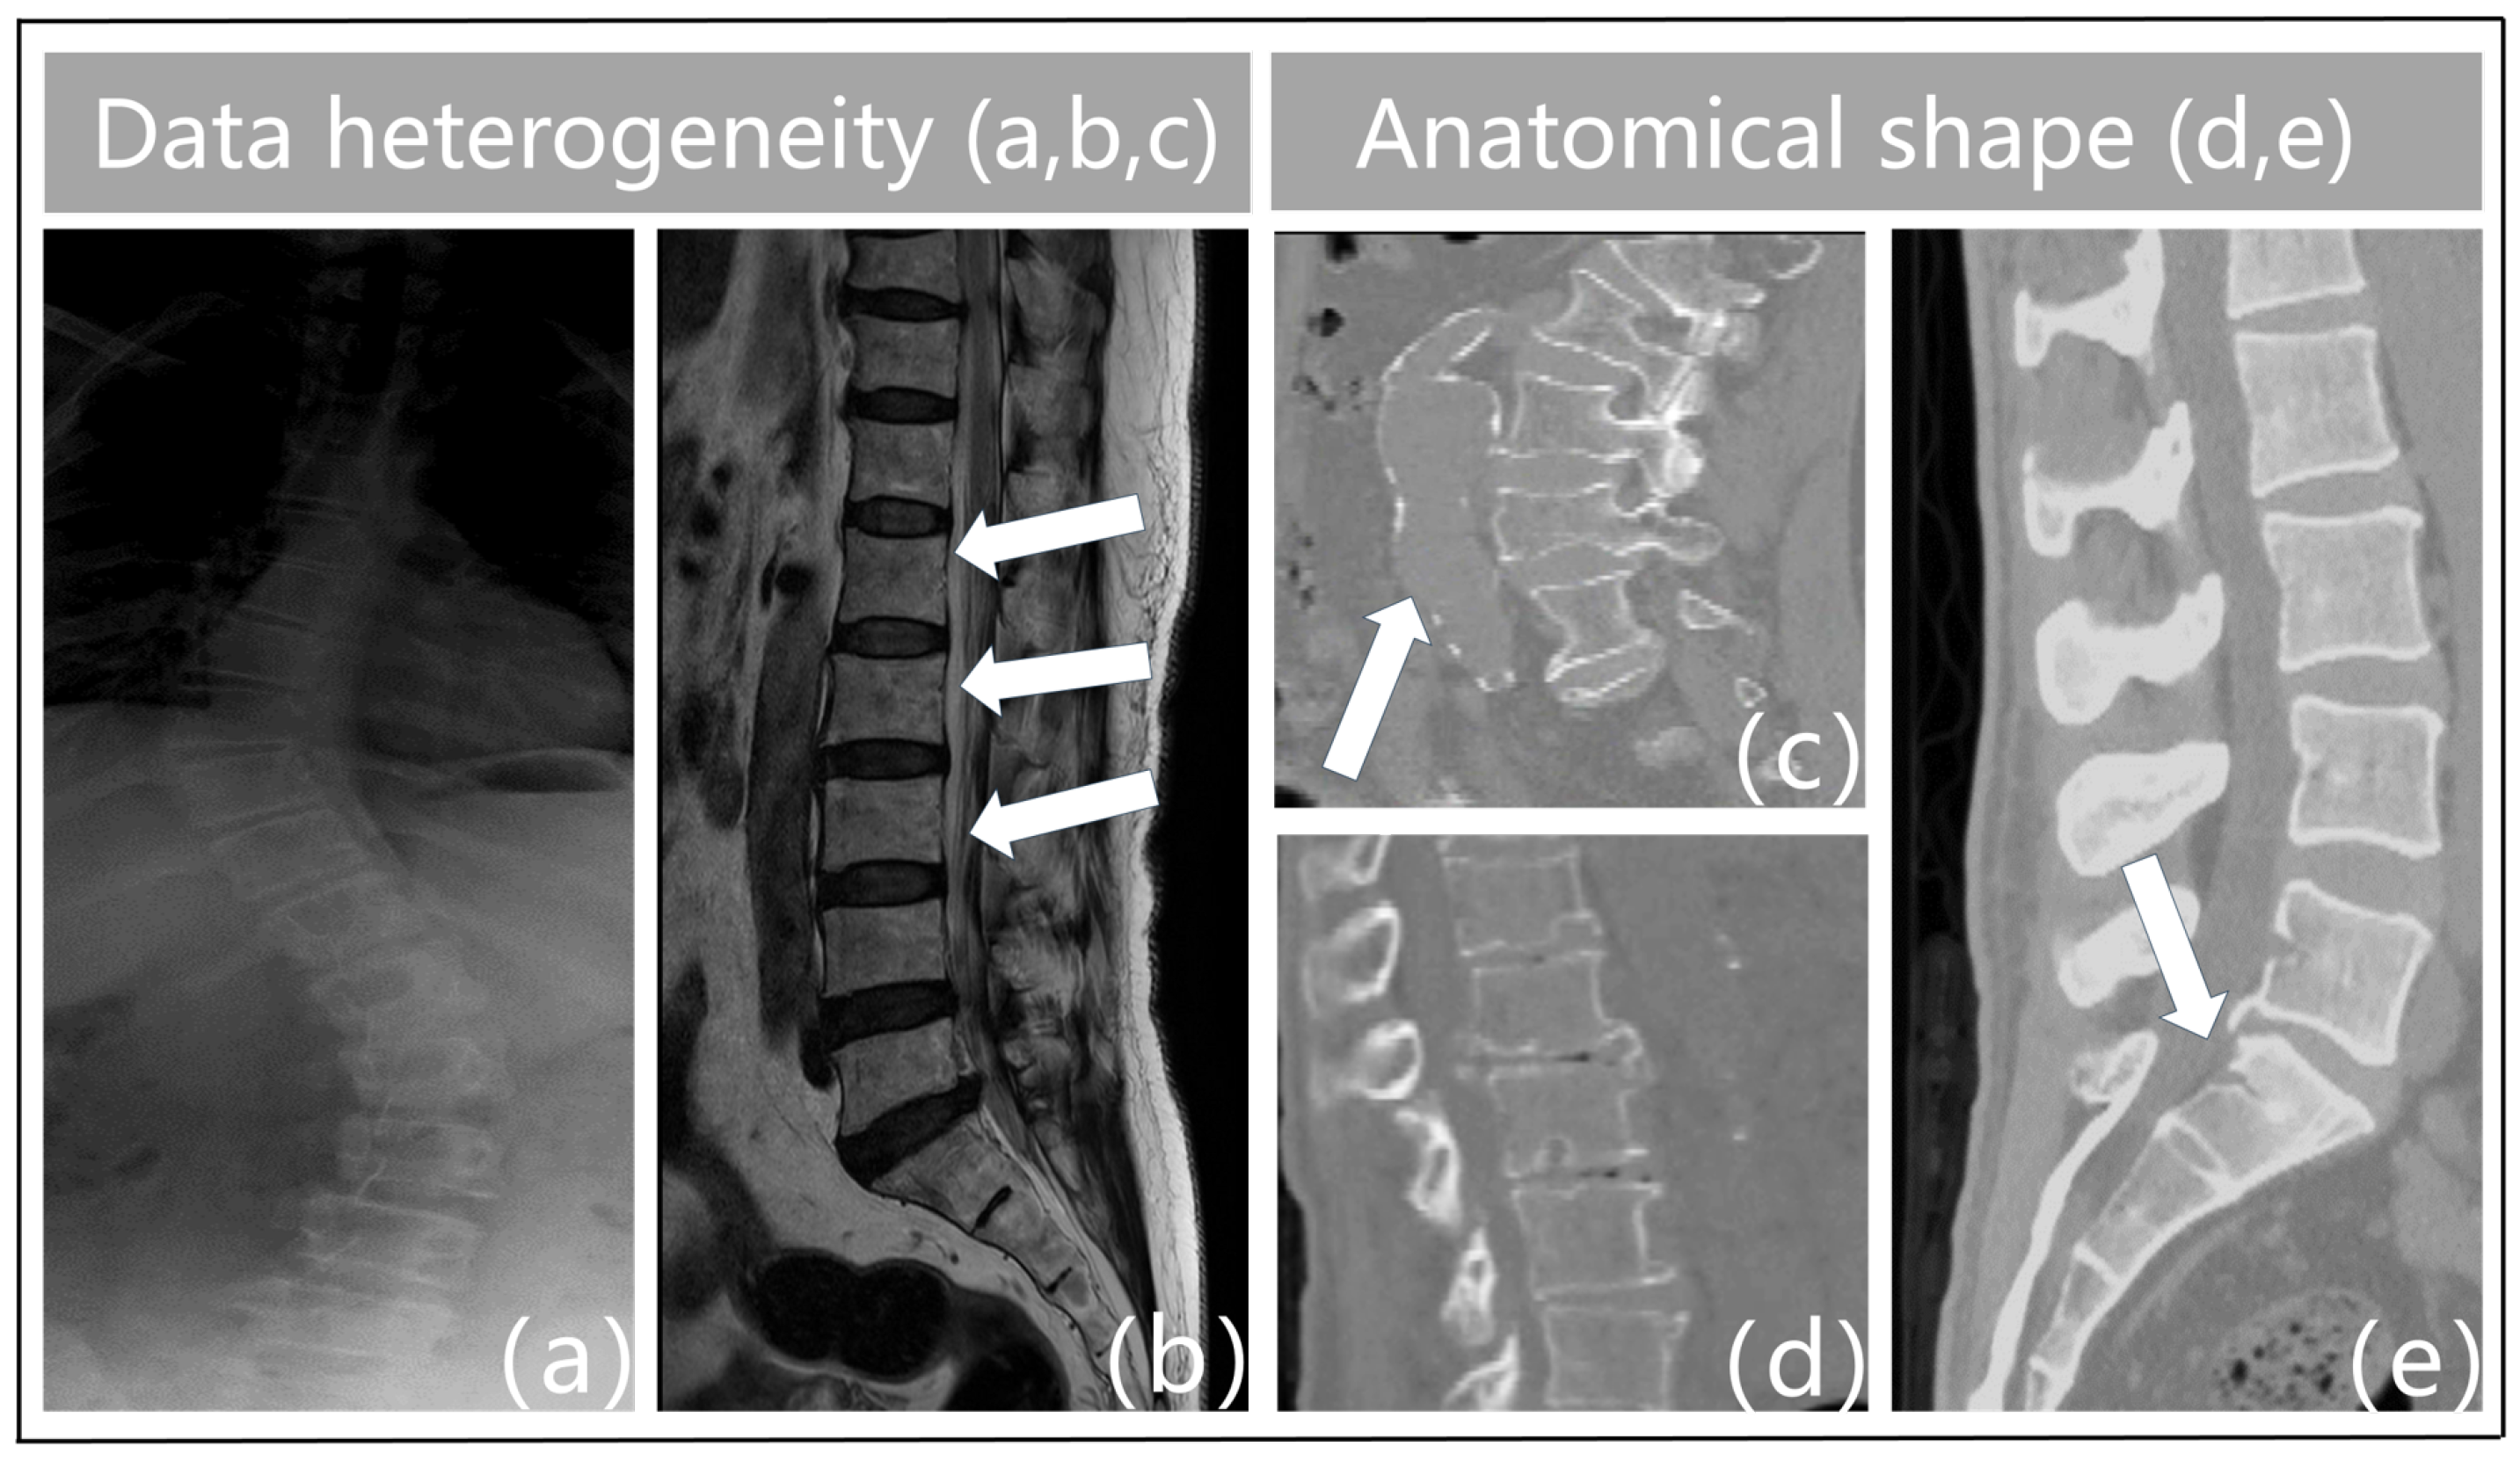

- Data heterogeneity. The term “heterogeneity of data” describes the variety and diversity of the data, or the variations in the data across various dimensions. These variations could be caused by a variety of things, including the characteristics of the chiropractic data itself, the acquisition technique, the equipment used, the duration of the acquisition, and more. For instance, feature extraction varies throughout different types of imaging data (e.g., MRI, X-ray, CT, etc.), and variations in acquisition equipment can result in issues with data quality such as noise and distortion in vertebrae imaging. Figure 1a illustrates the blurred outlines caused by the physical properties of X-ray imaging. Second, interclass similarity is seen in spinal MR images [5]. This means that neighboring vertebrae (intervertebral disks) in the same subject (Figure 1b) exhibit a high degree of morphological resemblance, making it more challenging to distinguish between individual vertebrae. The surrounding tissues in Figure 1c have similar physics and tissue densities to the vertebrae in CT imaging, which leads to identical CT values that confuse the background features and result in erroneous detections. Analogously, variations in the duration of acquisition may cause data drift and variability. As a result, data heterogeneity must be taken into account and managed throughout data processing and analysis since it is one of the key elements influencing the outcomes of data analysis and mining.

- Anatomical shape. Vertebral pictures show features such as blurriness, uneven grayscale distribution, high noise levels, and low contrast because of the state of spinal medical imaging today. The vertebrae that make up the spinal structure also have a similar form but different types. Spinal illnesses like vertebral strain alter the anatomical form of the vertebral bodies, as shown in Figure 1d. Furthermore, the vertebrae are spatially displaced as a result of trauma, bad posture, muscular imbalance, and congenital deformities [7]. This causes aberrant modifications or misalignment of their locations in space, which severely distorts the morphology of the vertebral bodies. Particularly, in Figure 1e, the individual had fractures or breaks in the sacral vertebrae as a consequence of external pressures. This may lead to further deformation, which makes the connections between the lumbar and sacral vertebrae extremely tight. As such, defining the borders between these joint vertebrae based on pixel intensity is difficult. This frequently results in semantic segmentation of these linked vertebrae as a single object during vertebral segmentation, which causes misidentification as a single vertebra. Given the increased unpredictability in the contour forms and placements of the vertebral bodies, these features surely make vertebral segmentation tasks more challenging.